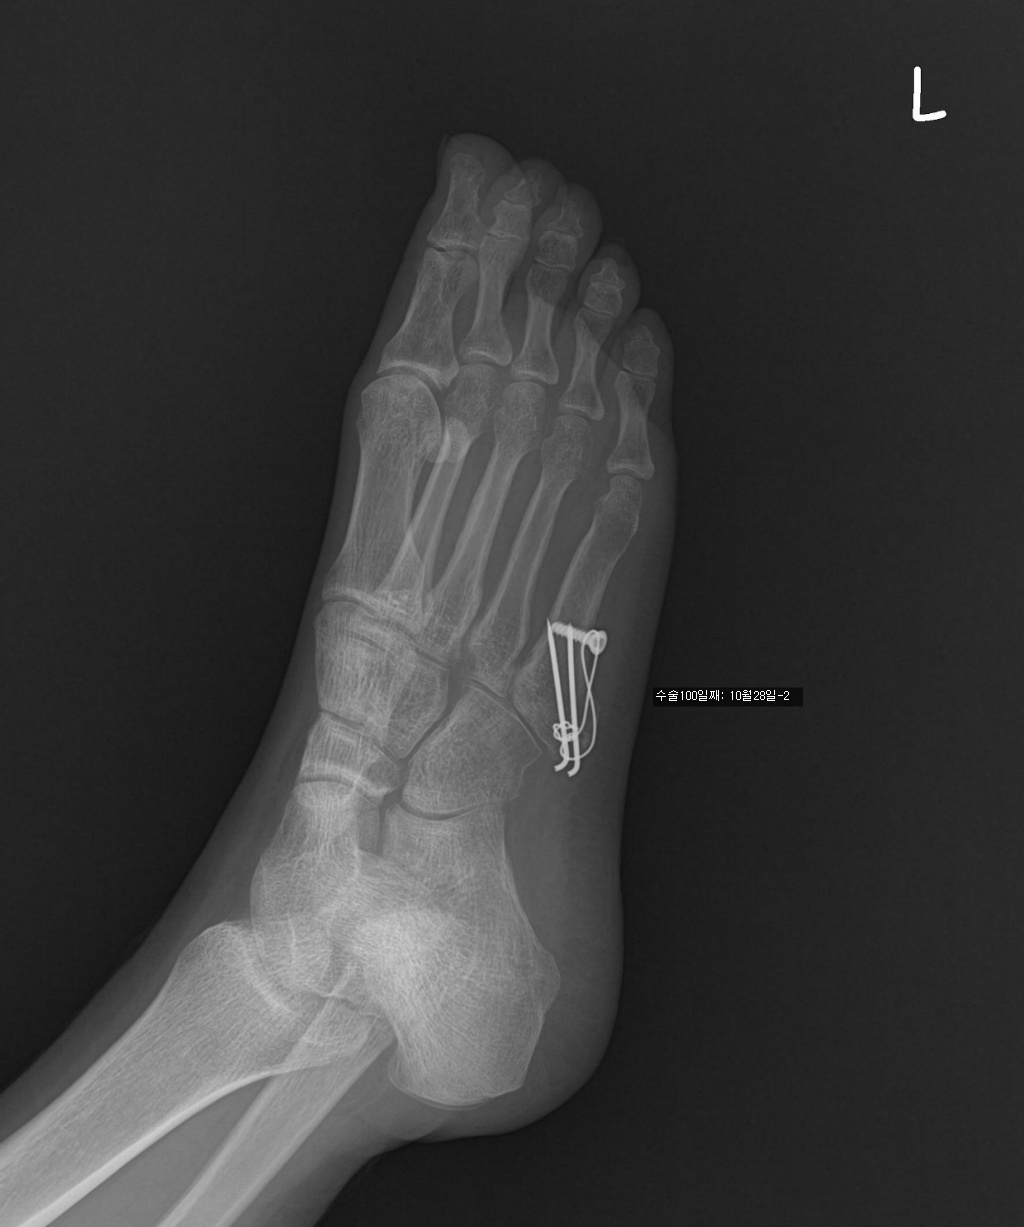

수술한지 100일 정도 됩니다.

7/17 : 출근 중 지하철 계단에서 구르는 사고로 좌측제5중족골기저부 골절

7/18 : 관헐적 정복 및 금속내고정술  시행 및 반깁스 (2주)

아래는 그간의 사진입니다. 제 눈은로는 수술직후의 사진과 3개월후의 사진의 차이를 잘 모르겠네요..